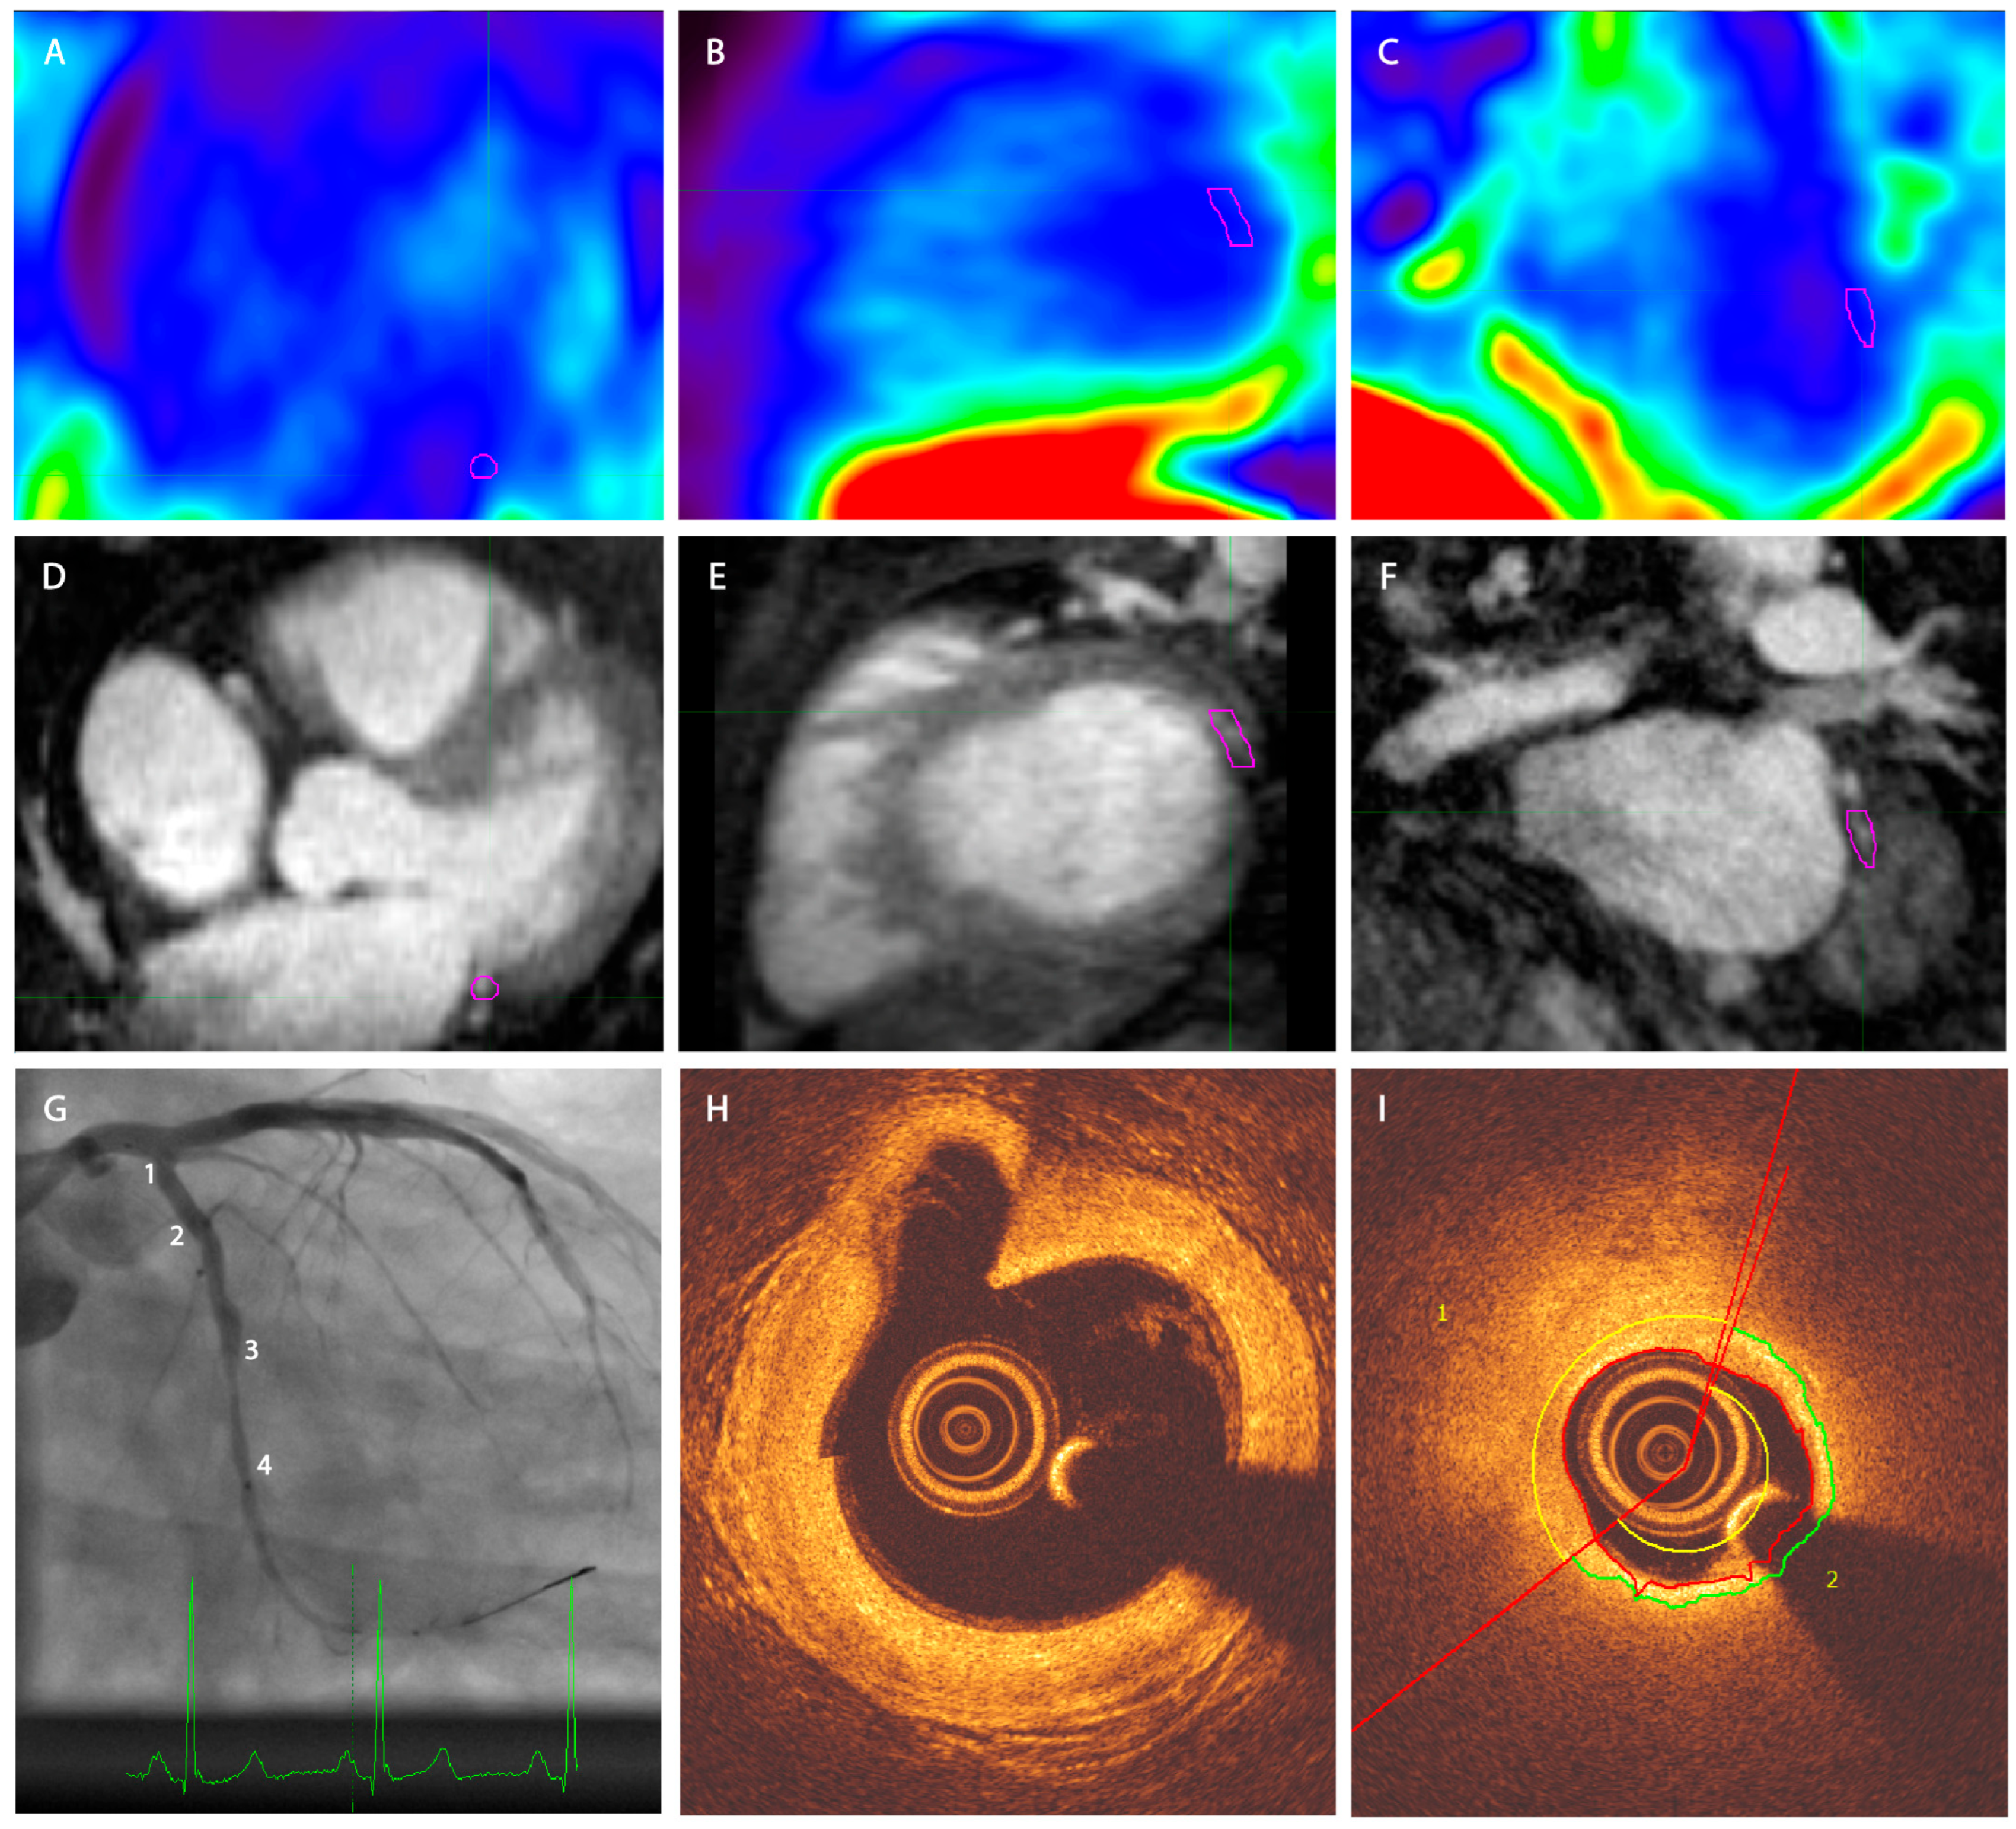

Molecular Imaging of Coronary Plaque Vulnerability Using 18F-Fluorocholine PET-MRI in Patients with Coronary Artery Disease: Validation with Optical Coherence Tomography

2.2. PET-MR Imaging

2.3. OCT Imaging

2.4. Image Reconstruction

2.5. Image Analysis